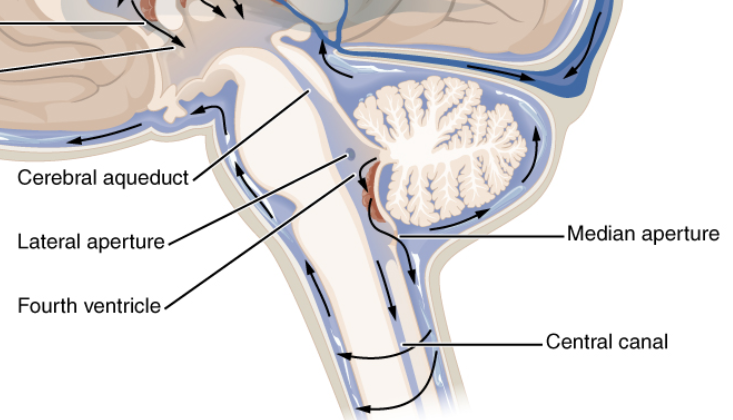

Which structure connects the 3rd to the 4th ventricle?

Cerebral aqueduct of Sylvius.

Where is the 4th ventricle located?

Between the pons and cerebellum.

How does CSF exit the 4th ventricle?

Via lateral and median apertures.

The 4th ventricle continues into what structure?

Central canal of the spinal cord.